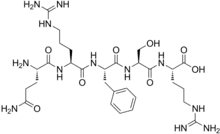

Others / unknown

- Adrenorphin

- Amidorphin

- Biphalin

- Casokefamide

- Casomorphins

- Cytochrophin-4

- DALDA (Tyr-D-Arg-Phe-Lys-NH2)

- Deltorphin I

- Deltorphin II

- Deprolorphin

- Dermorphin

- DPDPE

Structures

| Other or unknown opioid peptides | ||||

|---|---|---|---|---|

Adrenorphin Adrenorphin |

Amidorphin Amidorphin |

Casomorphin Casomorphin |

DALDA DALDA |

|

DPDPE DPDPE |

Endomorphin-1 Endomorphin-1 Endomorphin-2 Endomorphin-2 |

Gliadorphin Gliadorphin |

Morphiceptin Morphiceptin | |

Nociceptin Nociceptin |

Octreotide Octreotide |

Opiorphin Opiorphin |

Rubiscolin Rubiscolin |

TRIMU 5 TRIMU 5 |